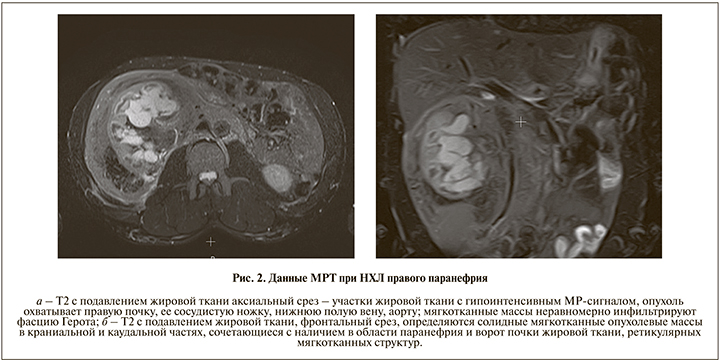

Выполнена мультипараметрическая полипозиционная МРТ брюшной полости в режимах Т1-, Т2-ВИ, диффузно-взвешенных изображений (DWI), Т2 с подавлением сигнала от жировой ткани, Т1-ВИ с внутривенным введением парамагнетика и динамическим контрастным усилением (ДКУ). На серии МР-томограмм брюшной полости до и после динамического контрастного усиления в правом забрюшинном пространстве определялась опухоль максимальным размером 217×178 мм, инфильтрирующая фасцию Герота, охватывающая правую почку, включая ее сосудистую ножку. Опухоль имела гетерогенное строение: мягкотканные массы неравномерно (от 7 до 18 мм) инфильтрировали фасцию Герота, определялись солидные мягкотканные опухолевые массы в краниальной (62–58 мм) и каудальной (63×74 мм) частях, сочетавшиеся с наличием в области паранефрия и ворот правой почки жировой ткани и ретикулярных мягкотканных структур (рис. 2). Опухолевые массы отображаются в виде гиперинтенсивного МР-сигнала на DWI-изображениях, охватывали по периметру правую почку с замедлением измеряемого по картам ACD коэффициента диффузии воды до 0,7 мм²/с (Н – коэффициент диффузии воды – 2,5 – 2,7 мм²/с, рис. 3), что характерно для злокачественных процессов.

Определяется выраженная фиксация парамагнетика в мягкотканных компонентах опухоли с относительно быстрым поступлением туда парамагнетика: коэффициент фиксации 0,576 относительно пика накопления в аорте (принимается за 1) и последующим постепенным повышением его концентрации в опухоли до 0,625 без признаков вымывания (злокачественный вариант кинетической кривой гемодинамики), наличие патологически измененных артериальных сосудов (рис. 4). Опухоль прилежала к нижней поверхности печени, головке поджелудочной железы, правой ножке диафрагмы. На фоне опухолевых масс правый надпочечник не определялся. Почечная сосудистая ножка, прилежащий сегмент нижней полой вены и аорты находились внутри опухолевых масс. Опухоль инфильтрирует нижнюю полую вену, брюшную аорту от бифуркации до печеночного сегмента, сливается с конгломератом увеличенных парааортальных, паракавальных лимфоузлов; смещает кишечник влево и кпереди, деформирует верхнюю брыжеечную артерию. Признаков нарушения уродинамики правой почки не выявлено, мочеточник не инфильтрирован, оттеснен влево. Определяется аномалия развития правой почки – множественные парапельвикальные кисты, почка увеличена в размерах, корковое вещество истончено. Печень без признаков очаговых изменений, левая доля увеличена, головка поджелудочной железы не визуализируется, тело и хвост без особенностей. Селезенка, левая почка без особенностей. В левом надпочечнике аденома размером 14×14 мм. Определяется жидкость в правом гемитораксе. Жидкость в брюшной полости не выявлена.